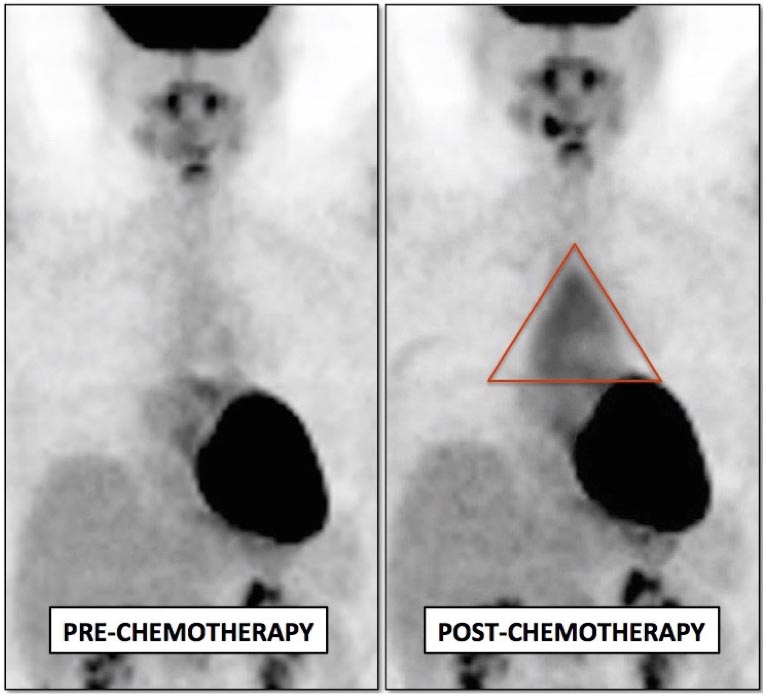

Thymic Rebound:

With stress (e.g. infection, surgery, burns, chemotherapy), the thymus may shrink to 2/3 its normal size. Upon recovery, the thymus typically returns to its normal size.

About 25% of patients, however, will experience a “rebound” overgrowth (hyperplasia) of the gland — up to 50% greater than its normal size. This enlarged gland often demonstrates significant metabolic activity, often intensely FDG-avid.

The enlarged gland should largely maintain its normal triangular configuration, without significant mass effect on the antero-lateral borders of the anterior mediastinum (“Thymic Rebound Hyperplasia” is discussed in greater detail, here).